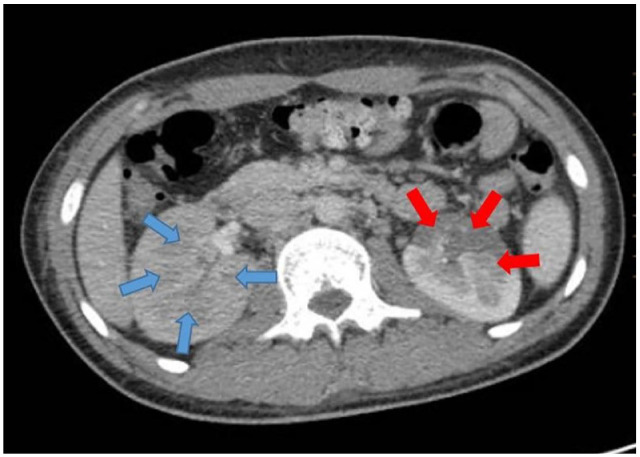

Case presentation: We report a case of 21-year-old man falling from a height of 9 m. A contrast-enhanced CT scan in the nephrogram phase showed no evidence of absorption in the right kidney and significantly decreased absorption in the left kidney. The pyelogram phase showed no secretion in the right kidney and decreased secretion in the left kidney suggesting segmental renal infarction. Subsequently, heparin infusion was initiated immediately. A follow-up contrast- enhanced abdominopelvic CT scan was performed after 1 month and showed no sign of infarction, and all laboratory tests were normal.